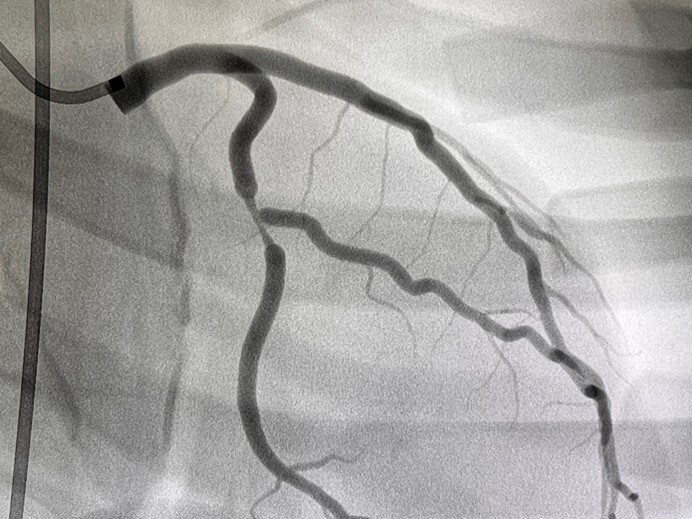

Abb. 4 Hauptstammstenose

Abb. 4: Hauptstammstenose (Mentice Vist)